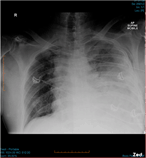

Traumatic diaphragmatic rupture with underlying lung laceration and tension pneumoperitoneum

Zexi Allan and others

Journal of Surgical Case Reports, Volume 2017, Issue 6, June 2017, rjx120, https://doi.org/10.1093/jscr/rjx120